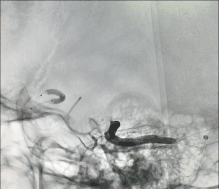

经静脉及动脉依次注射ONYX18约4ml,注胶时,球囊的阻断起到了关键作用(高压锅技术)。

静脉端持续打胶。

术后造影见AVM已经完全栓塞。